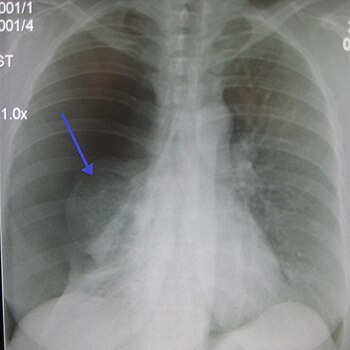

A large right-sided spontaneous pneumothorax (left in the image). An arrow indicates the edge of the collapsed lung

Recurrent or persistent pneumothorax

The simplest and earliest procedure was to introduce air into the pleural space so as to collapse the affected lung and therefore the open cavity. There was always spontaneous resolution of the pneumothorax and the procedure had to be repeated every few weeks.